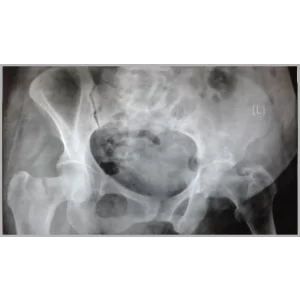

Details of Right Total Hip Replacement And Right Total Knee Replacement In Single Stage Only